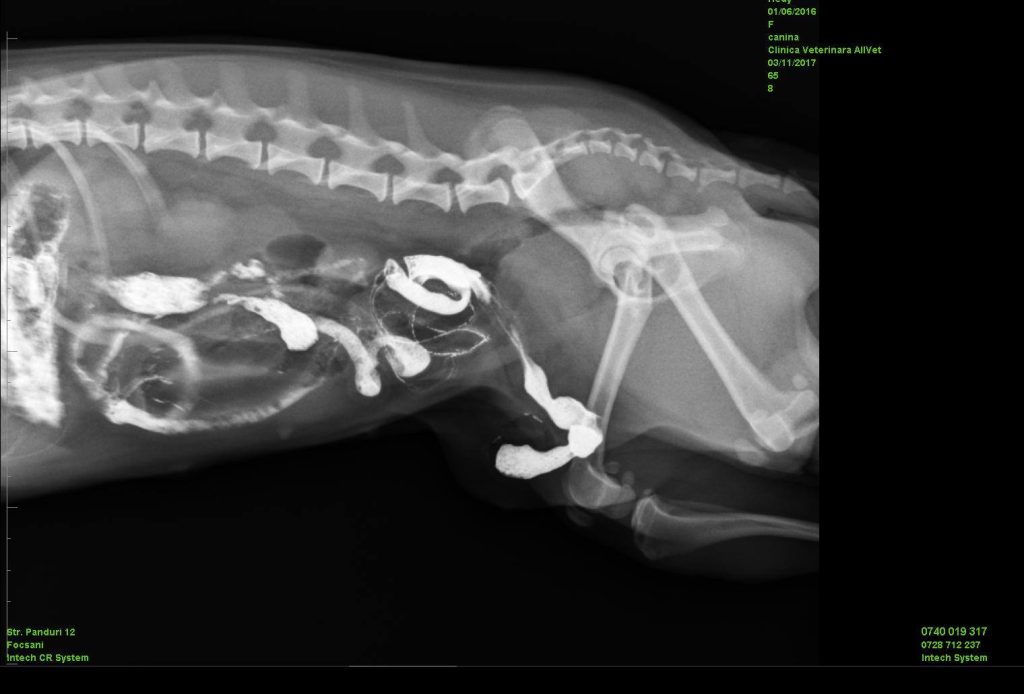

Radiologie Veterinara Digitala

Share this post : Facebook Twitter Linkedin Recent am introdus, ca parte in procesul de diagnostic, examinarea radiologica. In urma consultului medical se stabileste utilitatea efectuarii unei radiografii. Serviciul de radiolgie, care sa efectueze radiografii la cerere, functioneaza doar pe baza de programare telefonica si cu trimitere scrisa de la medicul veterinar curant, cu expunerile […]